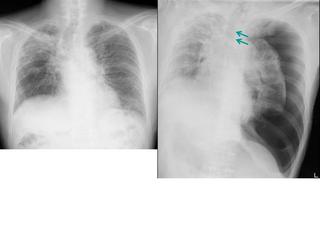

こちらを見て下さい。

わかりにくいかもしれませんが、このあたり。

気管が追いにくい、無くなっているようにも見えます。

気管狭窄ですね。こういう所見もレントゲンで捉えることができるのです。